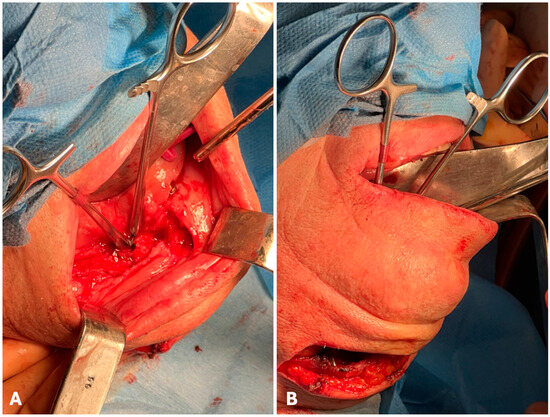

2. Case Description